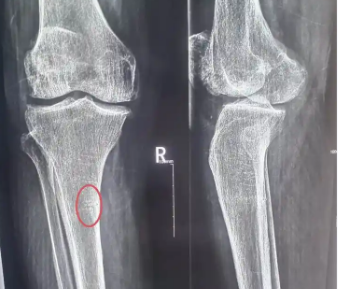

骨折的主要症状有哪些?

骨折的主要症状包括局部疼痛、肿胀、畸形、功能障碍和异常活动。骨折通常由外伤、骨质疏松、病理性骨折等因素引起,建议及时就医进行X线检查以明确诊断。1、局部疼痛 骨折后局部会出现剧烈疼痛,活动时疼痛加重,按压骨折部位时疼痛明显。疼痛可能与骨折端移位刺激周围神经有关。患...